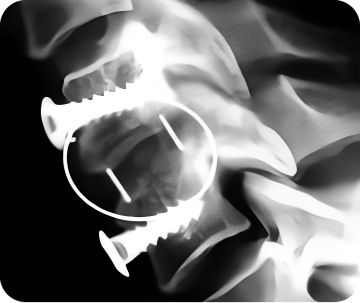

SHIVAS®, ISIS®, DEXTER™

Линейка кейджей из полимерного материала PEEK-Optima. В состав линейки входят кейджи для межтелового спондилодеза в шейном, грудном и поясничном отделах позвоночника.

Материал: полиэфирэфиркетонВысокая биосовместимость материалаШирокий ассортимент всех видов кейджейРентгеноконтрастные маркеры для визуализации на рентгенограммах и облегчения правильного позиционированияЗубцы на верхней и нижней поверхности кейджей для уменьшения вероятности их миграции

Полости для заполнения их костным материаломИзогнутые поверхности в соответствии с рельефом замыкательных пластинПростота установки